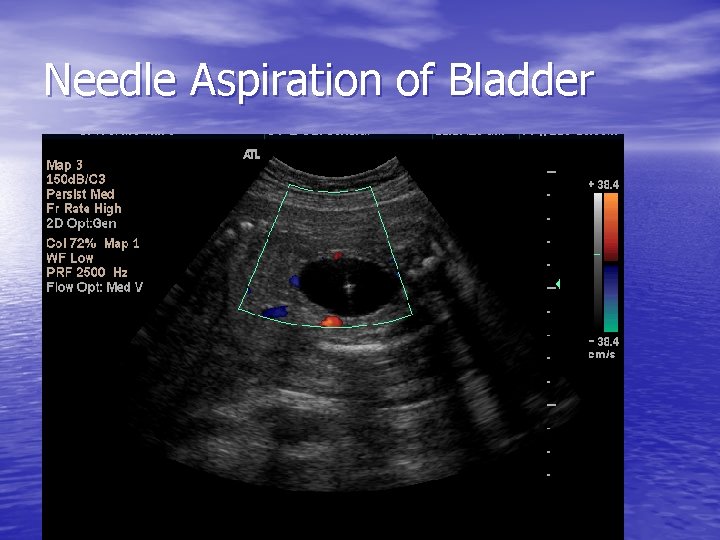

Needle Aspiration of Bladder

Work up – First step – ultrasound • Bladder evaluated prior to and following • • drainage by fine needle vesicocentesis Overall size of bladder and degree of proximal urethral dilation (keyhole sign) Urethral and kidney evaluation for dilation or abnormalities, echogenicity, or cysts After vesicocentesis – the degree of bladder thickness is assessed Rule out other anomalies ie NTD, cardiac defects

Final Eval – Third step • Evaluation of fetal kidney function with sequential vesicocenteses • Completely drain fetal bladder at 48 -72 hr intervals at a minimum of three occasions • Fetuses w/ progressive hypotonicity and values that fall below threshold benefit from in utero intervention i. e. shunt placement

Eval cont • Fetuses with isolated megacystis, bilateral hydronephrosis, decreased amniotic fluid volume, absent anomalies, a 46 XY karyotype and serially improving hypotonicity with values below the recommended thresholds would be candidates for vesicoamniotic shunt placement